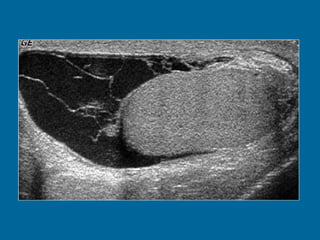

cystic mass  (M) with echogenic borders and peripheral solid components (arrows). A rim of normal testis  (T) is also seen